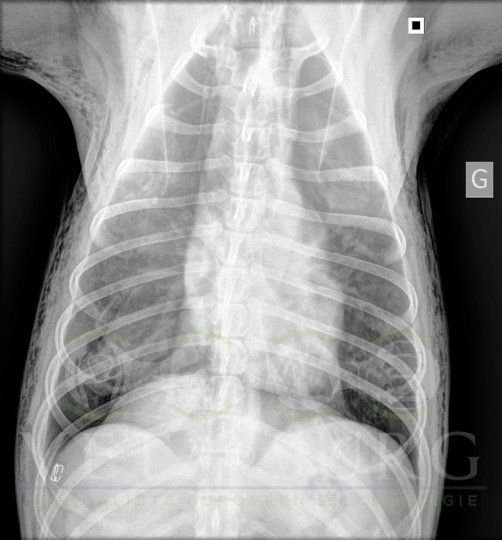

Dans la gestion des pathologies respiratoires, cardio-vasculaires, et des atteintes médiastinales et diaphragmatiques.